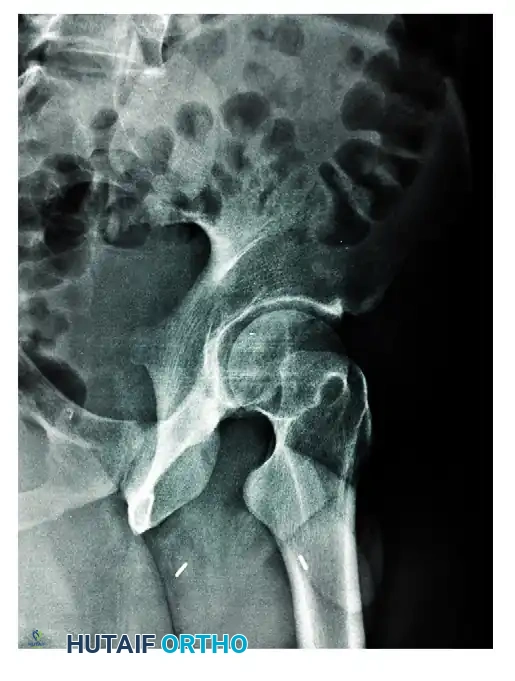

The Obturator Oblique View

In the obturator oblique view, the patient is rolled 45 degrees toward the injured side (elevating the uninjured hip). The radiographic beam is directed roughly perpendicular to the obturator foramen of the affected side.

* Primary Structures Visualized: This view places the obturator ring en face, providing a true profile of the anterior column and the posterior wall of the acetabulum.

* Diagnostic Utility: It is the definitive view for assessing the iliopectineal line's distal extent, the obturator ring, and the size and displacement of posterior wall fracture fragments.